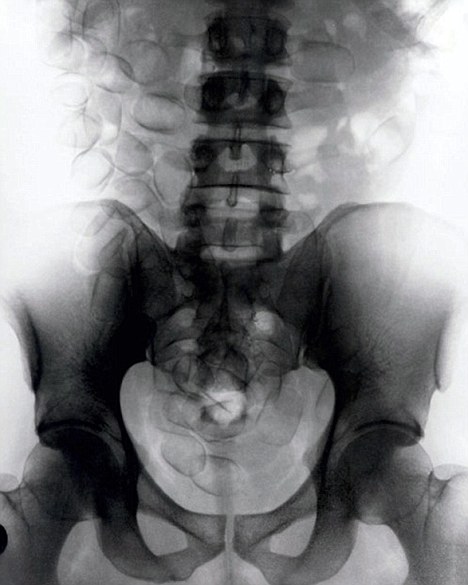

現年30歲的菲達利斯(Fidelis Ozouli)冒著生命危險將重達1公斤的毒品吞下,被抓后卻辯稱不知道吞下的是毒品。當時,曼徹斯特機場的海關人員看到毒販菲達利斯臃腫的肚腩,顯得很不自然,于是開始懷疑。檢查人員用X射線機照他的胃部時,發現了大量可卡因。目前他已被送往附近醫院,以確保排出所有的毒品。